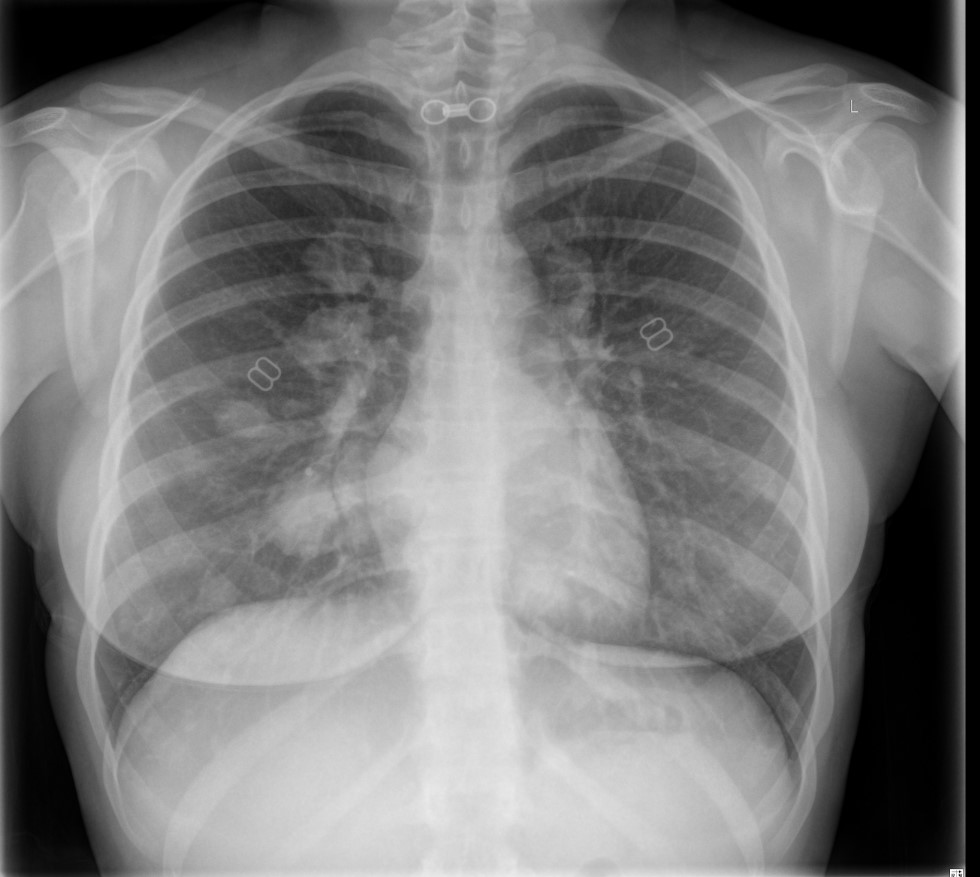

Chest Xray

Chest metastasis